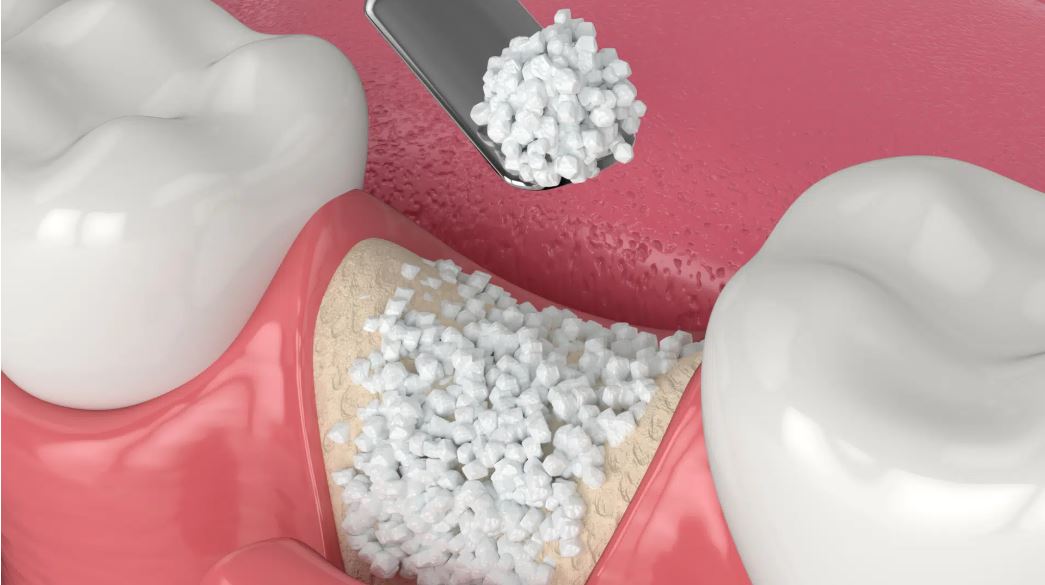

- Hạn chế tình trạng tiêu xương hàm: Mất răng toàn hàm dẫn đến hiện tượng tiêu xương một cách nhanh chóng, cấu trúc gương mặt cũng thay đổi và dẫn đến rối loạn khớp thái dương hàm.

Tuy nhiên, khi thực hiện cấy ghép All On 4, trụ Implant sẽ được cắm vào những vị trí thích hợp, thay thế chân răng thật và tạo lực kích thích lên xương hàm. Vì vậy, ngăn chặn hoàn toàn tình trạng tiêu xương và duy trì hình dạng khuôn mặt tự nhiên, trẻ trung.